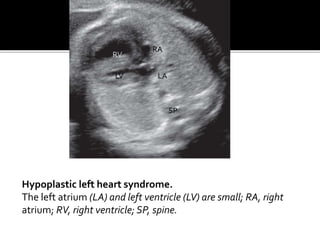

Hypoplastic left heart syndrome.

The left atrium (LA) and left ventricle (LV) are small; RA, right

atrium; RV, right ventricle; SP, spine.

 8% ofall CHDs .  Small left ventricle due to decresed blood flow in and out of left ventricle .  Primary abnormalities –aortic stenosis,aortic atresias ,and mitral valve atresias .80% cases associated with COARCTATION OF AORTA .  Color doppler shows absence of flow through the mitral and aortic valves .

Hypoplastic left heartsyndrome. The left atrium (LA) and left ventricle (LV) are small; RA, right atrium; RV, right ventricle; SP, spine. RV LV SP RA LA